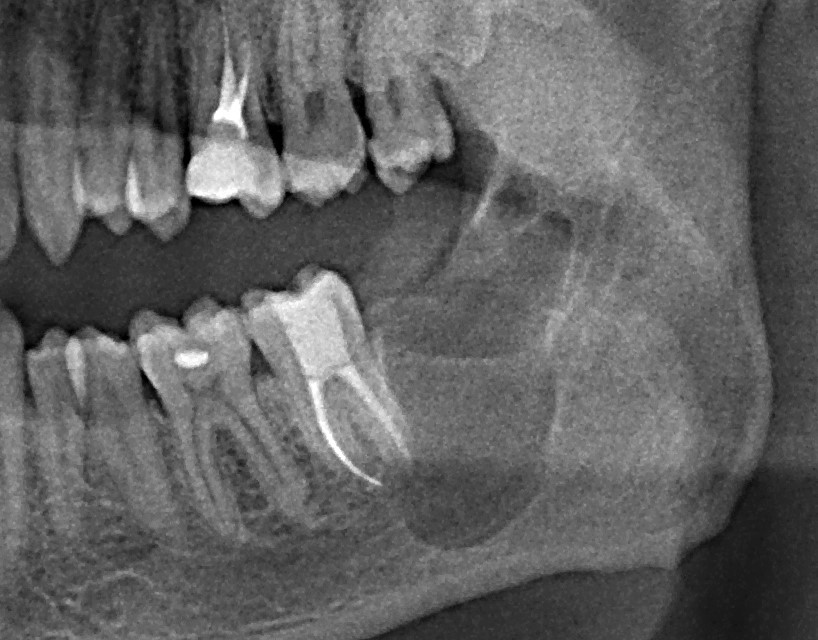

Это, кстати, значит, что в пограничных случаях (например, при расстоянии АБ=8 мм и длине имплантата 9 мм) мы можем вполне себе обойтись без синуслифтинга, поскольку попадание верхушки имплантата в просвет верхнечелюстного синуса на 1-1,5 мм не несёт в себе каких-либо рисков. Более того, если мы с вами сделаем и изучим КЛКТ пациентов с имплантатами и т . н. «закрытым» синуслифтингом, проведенным 5-6 лет назад, то увидим, что в половине случаев верхушки имплантов так или иначе выходят в просвет гайморовой пазухи:

Другими словами, не парьтесь. Риск от операции синуслифтинга, даже закрытого, выше, чем вероятность осложнений от попадания двух витков имплантата в просвет верхнечелюстной полости. Не усложняйте жизнь себе и вашим пациентам — если расстояние до дна пазухи меньше желаемой длины имплантата на 1 мм — просто ставьте имплантат. И все будут счастливы.